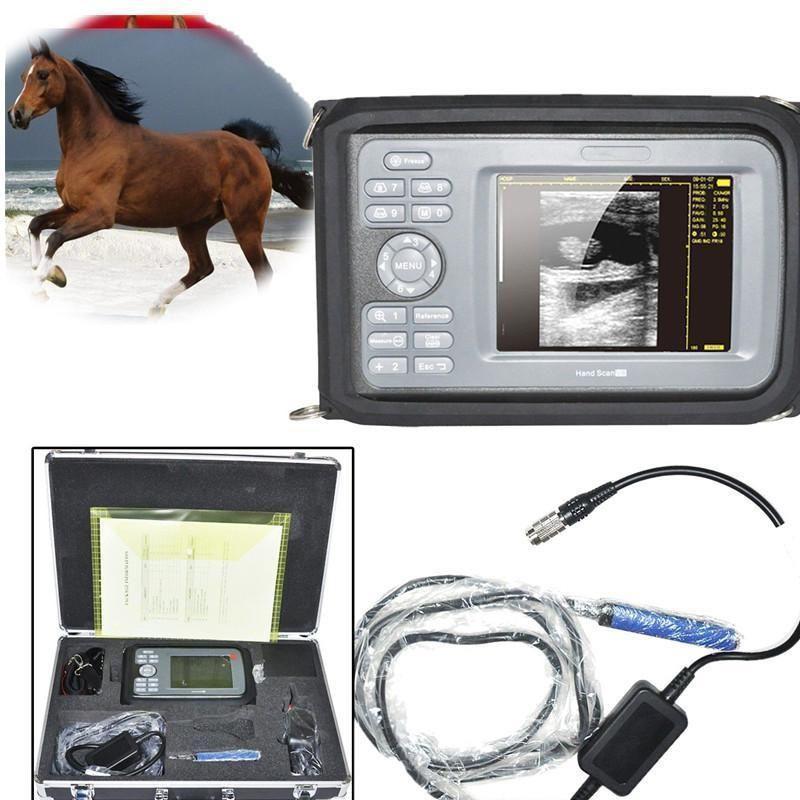

Veterinary VET Digital Palm ultrasound scanner Big Animal Rectal probe Lovestock 190891226921

Sale price$ 1,596.53

Regular price$ 1,946.99

Veterinary VET Digital Palm Ultrasound Scanner Machine Big Animals Rectal Probe 190891226921

Sale price$ 1,596.53

Regular price$ 1,946.99

Veterinary VET Digital Scan Ultrasound Scanner Machine Big Animals Rectal Probe 190891226921

Sale price$ 1,596.53

Regular price$ 1,946.99